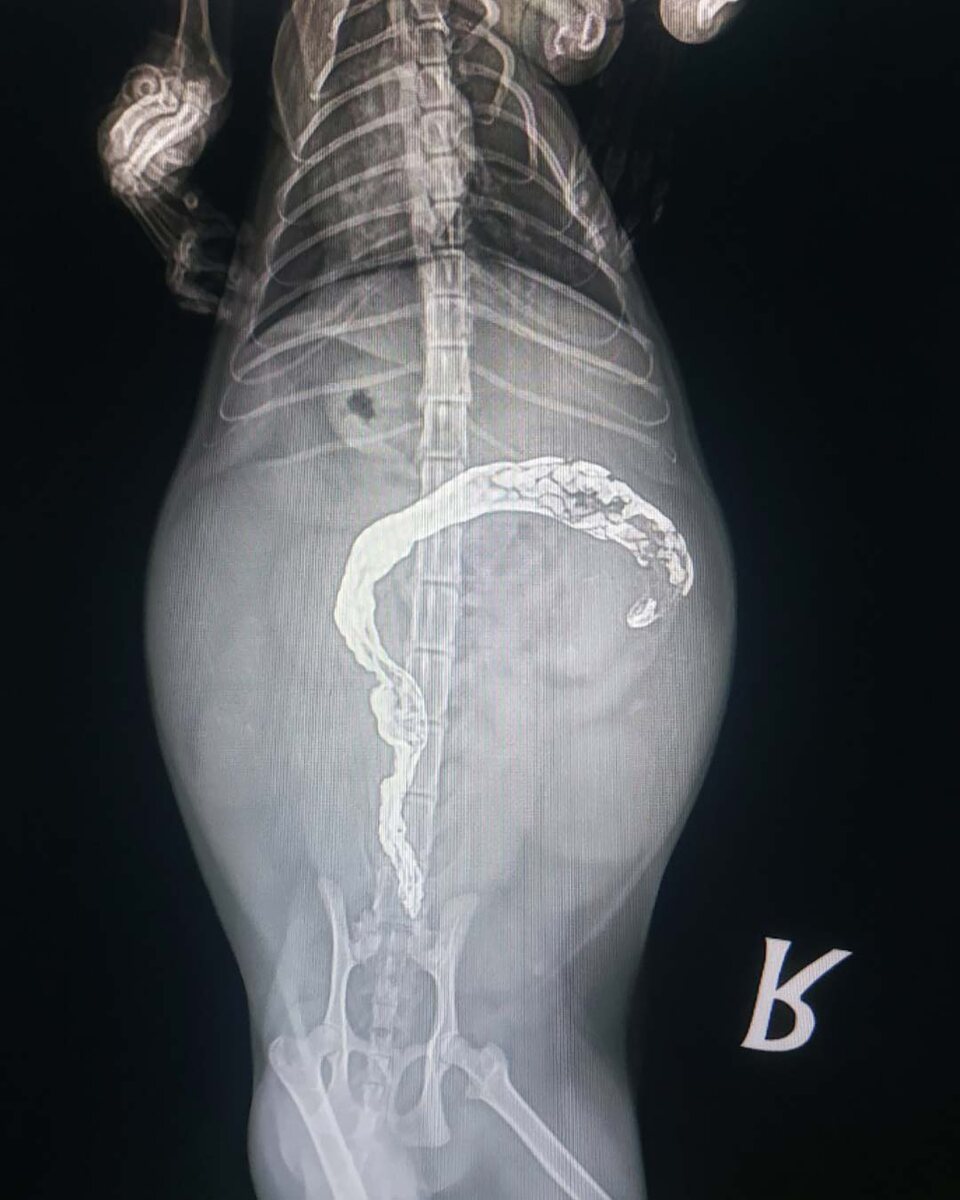

Рвота трихобезоарами (шерстяные комочки) у кошки, нормально или нет? Отвечаю, нет. На этом можно закончить мой пост 😄 но конечно же я не закончу и расскажу чуть подробнее об этом. То, что это норма, это навязанное понимание. Ведь всегда так было, это популяризируют в средствах массовой информации, об этом говорят все друзья и знакомые. Но это не норма. Шерсть должна выходить из организма кошки естественным путем. Рвота - это не естественный путь, а патологический. Естественный - это через кишечник, с каловыми массами. Мы разобрались, что это патология. Давайте разберемся, как избежать этого. Первым, способом является регулярный груминг. Чем меньше шерсти проглатывает кошка, тем меньше её в пищеварительном тракте. Второй способ - это использование специализированных мальт-софт паст для вывода шерсти. Сейчас их огромное разнообразие, есть даже для кошек с пищевой гиперчувствительностью (они не содержат с своем составе мясных добавок). Третий способ - использование кормов с пометкой Hair